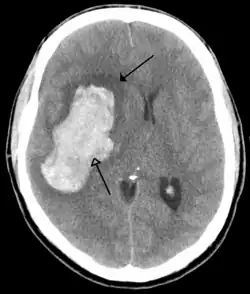

CT scan of a cerebral hemorrhage, showing an intraparenchymal bleed (bottom arrow) with surrounding edema (top arrow)

A stroke is a decrease in blood supply to an area of the brain causing cell death and brain injury. This can lead to a wide range of symptoms, including the "FAST" symptoms of facial droop, arm weakness, and speech difficulties (including with speaking and finding words or forming sentences).[191] Symptoms relate to the function of the affected area of the brain and can point to the likely site and cause of the stroke. Difficulties with movement, speech, or sight usually relate to the cerebrum, whereas imbalance, double vision, vertigo and symptoms affecting more than one side of the body usually relate to the brainstem or cerebellum.[192]

Most strokes result from loss of blood supply, typically because of an embolus, rupture of a fatty plaque causing thrombus, or narrowing of small arteries. Strokes can also result from bleeding within the brain.[193] Transient ischaemic attacks (TIAs) are strokes in which symptoms resolve within 24 hours.[193] Investigation into the stroke will involve a medical examination (including a neurological examination) and the taking of a medical history, focusing on the duration of the symptoms and risk factors (including high blood pressure, atrial fibrillation, and smoking).[194] Further investigation is needed in younger patients.[195] An ECG and biotelemetry may be conducted to identify atrial fibrillation; an ultrasound can investigate narrowing of the carotid arteries; an echocardiogram can be used to look for clots within the heart, diseases of the heart valves or the presence of a patent foramen ovale.[195] Blood tests are routinely done as part of the workup including diabetes tests and a lipid profile.[195]

Some treatments for stroke are time-critical. These include clot dissolution or surgical removal of a clot for ischaemic strokes, and decompression for haemorrhagic strokes.[196][197] As stroke is time critical,[198] hospitals and even pre-hospital care of stroke involves expedited investigations – usually a CT scan to investigate for a haemorrhagic stroke and a CT or MR angiogram to evaluate arteries that supply the brain.[195] MRI scans, not as widely available, may be able to demonstrate the affected area of the brain more accurately, particularly with ischaemic stroke.[195]